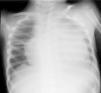

El sexto día de ingreso presenta empeoramiento del estado general, quejándose de dolor abdominal tipo cólico. A la exploración física, destaca taquipnea, taquicardia e hipotensión, y se auscultan ruidos cardíacos atenuados. Se realiza una radiografía de tórax donde se objetiva una cardiomegalia con índice cardiotorácico de 0,73 (fig. 1). El electrocardiograma mostró bajo voltaje, con elevación del segmento ST de manera difusa (fig. 2). Se realiza una ecocardiografía, que confirma la presencia de derrame pericárdico grave, sin signos de taponamiento, con fracción de eyección del ventrículo izquierdo (FEVI) conservada. Se realiza una pericardiocentesis ecodirigida y se obtienen 300ml de un líquido serohemático, con características de trasudado (pH 7,35, hematíes 11.750/μl, leucocitos 847/μl [84% neutrófilos], glucosa 79mg/dl, proteínas 45g/l), dejándose colocado un tubo de drenaje pericárdico. El cultivo de este líquido fue negativo.